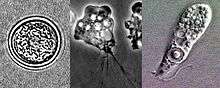

| the stages flagellate, trophozoite and cyst (seen from upper left to lower left to right) of Naegleria fowleri | |

Life cycle

Naegleria fowleri is a thermophilic (heat-loving), free-living amoeba. It is found in warm and hot freshwater ponds, lakes and rivers, and in the very warm water of hot springs. As the water temperature rises, its numbers increase. It was first discovered in 1965, and first identified in Australia.[3] N. fowleri occurs in three forms – as a cyst, a trophozoite (ameboid), and a biflagellate (it has two flagella). It does not form a cyst in human tissue, where only the amoeboid trophozoite stage exists. The flagellate form can exist in the cerebrospinal fluid.

Cyst stage

The cyst form is spherical and about 7-15 µm in diameter. They are smooth, and have a single-layered wall with a single nucleus. Cysts are naturally resistant to environmental factors, so as to increase the chances of survival until better conditions occur. Trophozoites encyst due to unfavorable conditions. Factors that induce cyst formation include a lack of food, overcrowding, desiccation, accumulation of waste products, and cold temperatures.[4] When conditions improve, the amoeba can escape through the pore, or ostiole, seen in the middle of the cyst. N. fowleri has been found to encyst at temperatures below 10 °C (50 °F).[5]

Trophozoite stage

The trophozoite is the feeding, dividing, and infective stage for humans. The trophozoite attaches to olfactory epithelium, where it follows the olfactory cell axon through the cribriform plate (in the nasal cavity) to the brain. This reproductive stage of the protozoan organism, which transforms near 25 °C (77 °F) and grows fastest around 42 °C (106.7 °F), proliferates by binary fission. The trophozoites are characterized by a nucleus and a surrounding halo. They travel by pseudopodia, which means that they extend parts of their body's cell membrane (the pseudopods) and then fill them with plasma to force locomotion. The pseudopods form at different points along the cell, thus allowing the trophozoite to change directions. In their free-living state, trophozoites feed on bacteria. In tissues, they phagocytize (consume by enclosing and then digesting prey) red blood cells and white blood cells, destroying tissue.[4]

Flagellate

The flagellate is pear-shaped and biflagellate: this means that it has two flagella. This stage can be inhaled into the nasal cavity during swimming or diving. This biflagellate form occurs when trophozoites are exposed to a change in ionic concentration, such as placement in distilled water. The flagellate form does not exist in human tissue, but can exist in the cerebrospinal fluid. Once inside the nasal cavity, the flagellated form transforms into a trophozoite. The transformation of trophozoite to flagellate occurs within a few hours.[4]